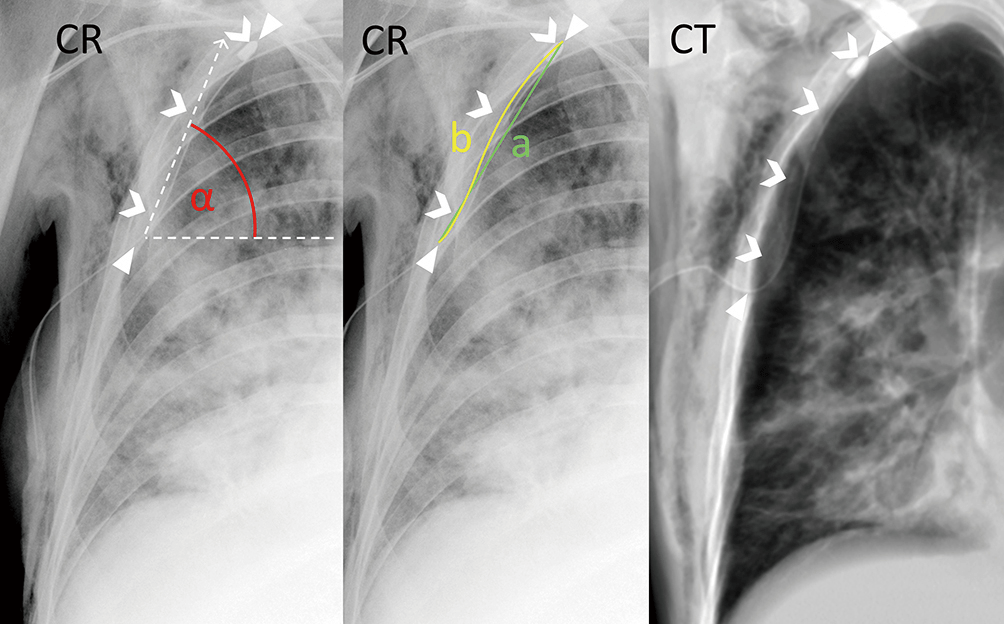

Below the left hemidiaphragm. The superiorinferior and mediallateral positioning of the tube can be determined on a chest x ray. Chest x ray interpretation tubes and lines duration. Chest x rays are commonly used to confirm correct positioning of certain medical devices and to check for associated complications following placement or misplacement.

This x ray was performed to check the position of a chest drain used to treat a pneumothorax conventionally this x ray would be considered inadequate for diagnostic purposes as it does not include the costophrenic angles the chest drain position is shown clearly the image does not need to be repeated to include the costophrenic angles. Ng tube tip 10 cm distal to the gastro esophageal junction. This tutorial describes the correct anatomical location following placement of common tube devices seen on chest x rays. Insertion into trachea or bronchus pneumoniapulmonary contusionpulmonary laceration.